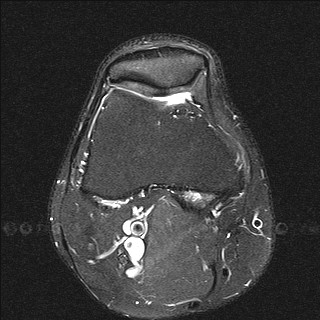

Результат МРТ правого лучезапястного сустава (рис. 2), подтвердил клиническое предположение о повреждении ладьевидно-полулунной связки, который заключался в нарушении целостности структуры связки. Также были выявлены признаки асептического некроза ладьевидной кости в стадии отека костной ткани.

Рис. 2. МРТ-исследование правого лучезапястного сустава. Получены протон взвешенные изображения с подавлением сигнала от жировой ткани (PD FAT SAT) в аксиальной, сагиттальной и фронтальной плоскостях, Т1 взвешенные изображения во фронтальной плоскости. На полученных сканах определяется: 1 – увеличение ладьевидно-полулунного сустава вдвое по сравнению с соседними; 2 – вдоль оси ладьевидной кости отмечается скопление жидкости, что можно расценить, как продольный перелом ладьевидной кости, либо отек костной ткани